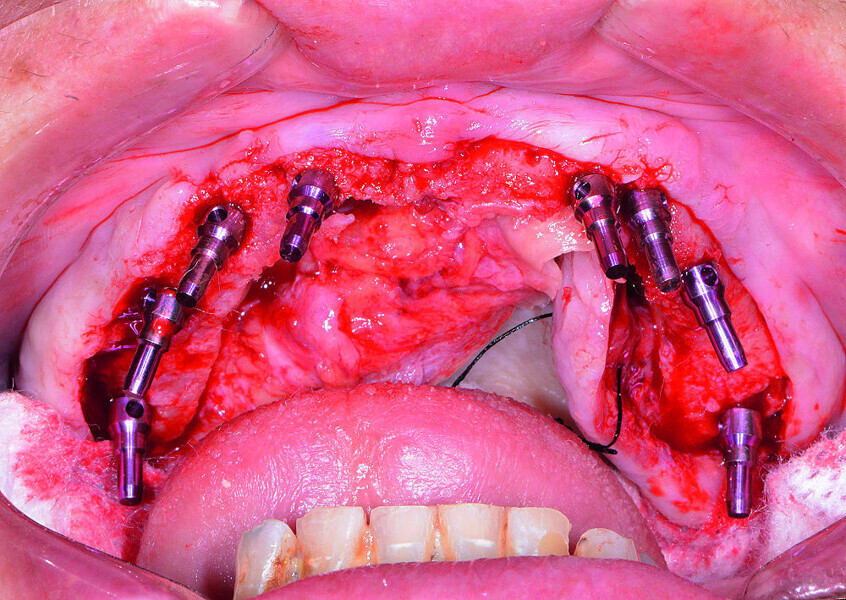

Fig 14 Guide chirurgical mandibulaire stabilisé